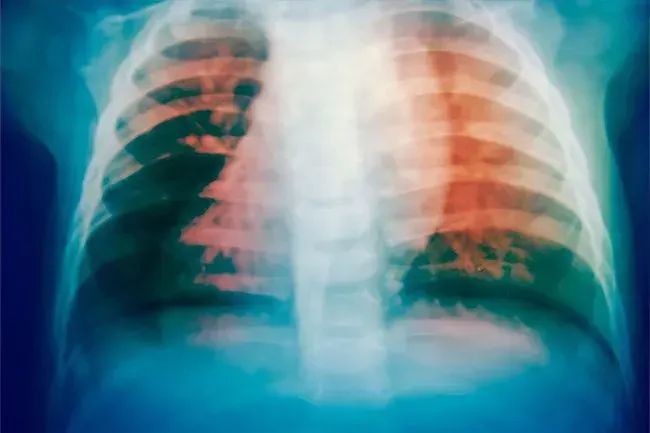

Tubercolosi

Circa la metà di tutte le persone che ricevono questa malattia hanno sudorazione notturna. I batteri di solito crescono nei polmoni. Probabilmente avrai una seria tosse dolorosa con sangue e gunk colorato (Phlegm). Potresti anche sentirti stanco e debole e non avere appetito.